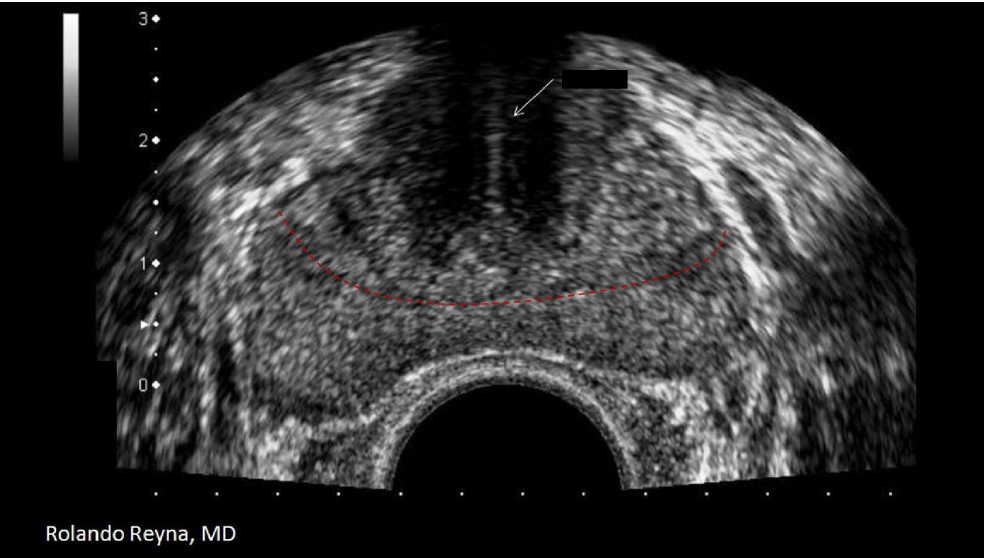

The red dotted line separates what two zones of the prostate?

B. transitional and peripheral

The white arrow indicates the urethra and the red dotted lines separate the transitional and peripheral zones.

The white arrow on the image indicates:

D. urethra